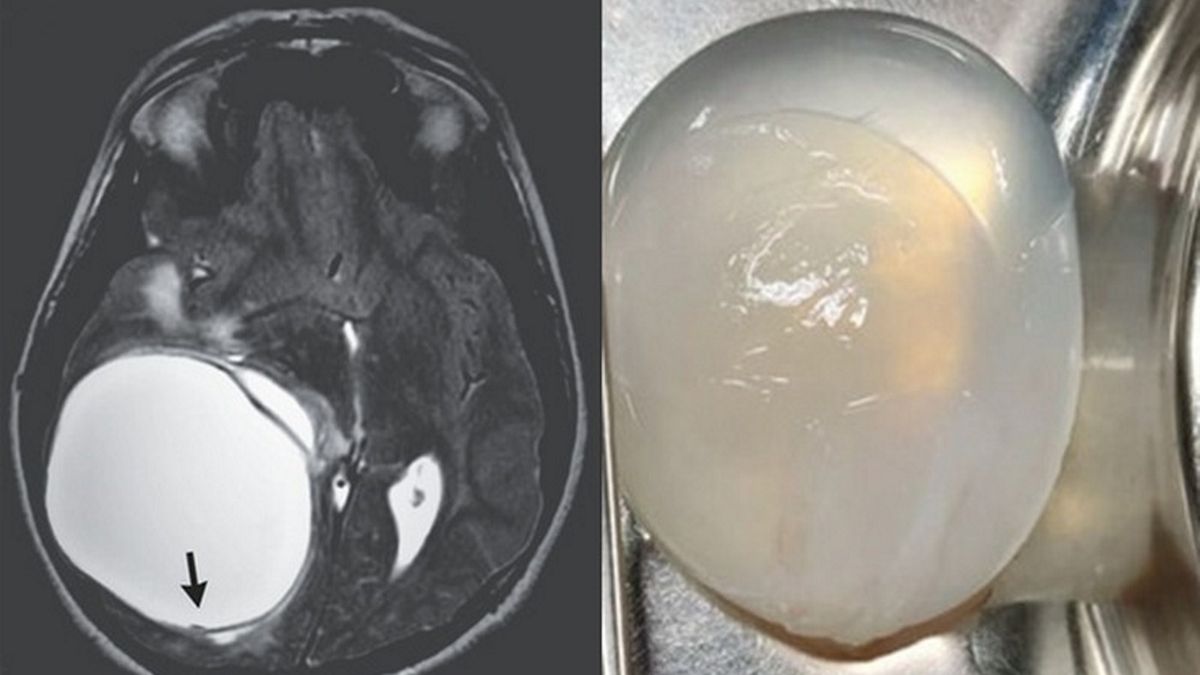

Źródło zdjęć: © The New England Journal of Medicine

Przypadek 14-latka z Indii został opisany w naukowym magazynie "The New England Journal of Medicine". Chłopiec zachorował na bąblowicę, ponieważ zaraził się tasiemcem – to właśnie pasożyt przenosi te niezwykle groźną dla zdrowia choroba.

Na temat niestandardowego przypadku medycznego zabrał głos doktor Sumit Thakar. Naukowiec z Oddziału Neurochirurgii w Instytucie Wyższych Nauk Medycznych Sathya Sai w Bangalore podkreślił, że nawet u pacjentów zarażonych bąblowicą rzadko dochodzi do wytworzenia się narośli. Stanowią oni zaledwie 2 proc. wszystkich chorych.

Tasiemiec dostał się do organizmu 14-latka, ponieważ chłopiec miał kontakt z zakażonymi zwierzętami lub odchodami. Narośl, jaka pojawiła się w głowie pacjenta, była wypełniona mlecznym płynem, zawierającym m.in. białka i lipidy. Aby ją usunąć, operujący nastolatka lekarze byli zmuszeni usunąć fragment czaszki.

Operującym 14-latka lekarzom udało się usunąć narośl bez dzielenia jej na mniejsze fragmenty. Było to konieczne ze względu na bezpieczeństwo pacjenta, ponieważ w przypadku wycieku płynu mogło dojść do reakcji alergicznej lub nawrotu schorzenia.

Ku uldze lekarzy i bliskim 14-latka, mimo rozmiarów narośl nie doprowadziła do uszkodzenia mózgu pacjenta. Ostatecznie spędził on w szpitalu dwa tygodnie, po których wypisano go z placówki medycznej, a on sam wrócił do nauki w szkole.